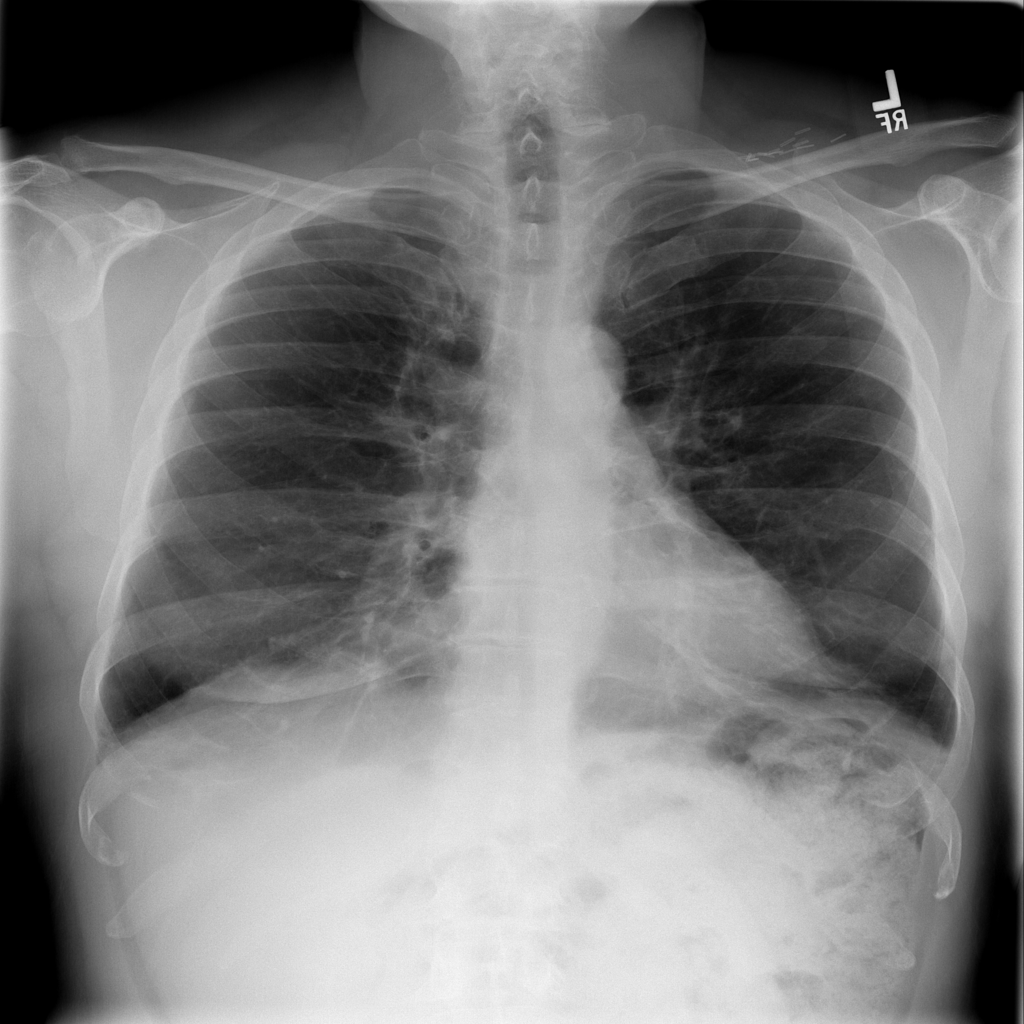

Pneumonia

Pneumonia is an infection of the lung tissue, often caused by bacteria, viruses, or less commonly fungi. On chest X-ray it can appear as focal or patchy air-space opacity, though imaging alone does not always prove the cause.

Showing up to 90 reference images for Pneumonia.

PAT-B3C3 · IMG-001Pneumonia

PAT-B3C3 · IMG-001

PA